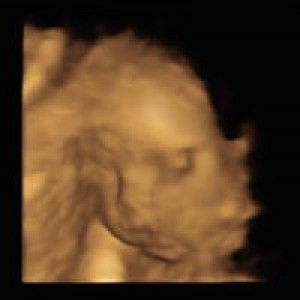

Hello Mamshie's. I am 31 weeks pregnant. My due date is on November 18, 2021. First time momma, first baby ko po. Ask ko lang po if kailan ako pwede mag start uminom ng pineapple juice? Or kumain ng pinya? Sabi po kasi nila pampa open daw po yun ng cervix. Thank you so much. #31weeks #pineapplejuice #pineapplefruit #firstbaby #firsttimemama